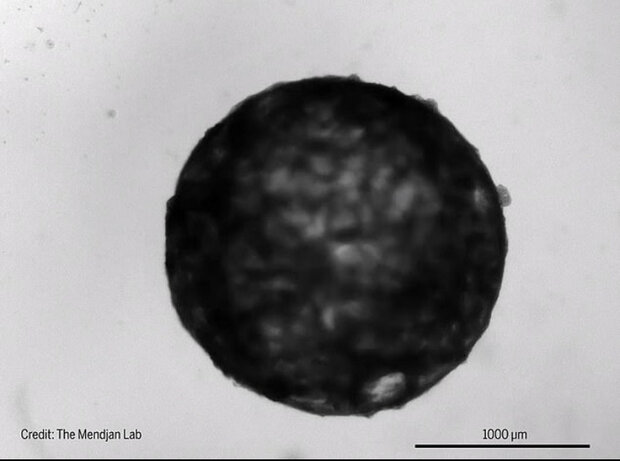

قلبی به اندازه دانه کنجد ساخته شد

ICTPRESS - محققان در آزمایشگاه نخستین مینی قلب انسان به اندازه دانه کنجد را ابداع کرده اند که می تپد و رفتار نطفه ۲۵روزه را تقلید می کند.